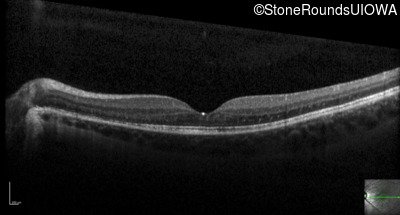

Optical Coherence Tomography - Left - 20/50

Exemplar / OCT Stack